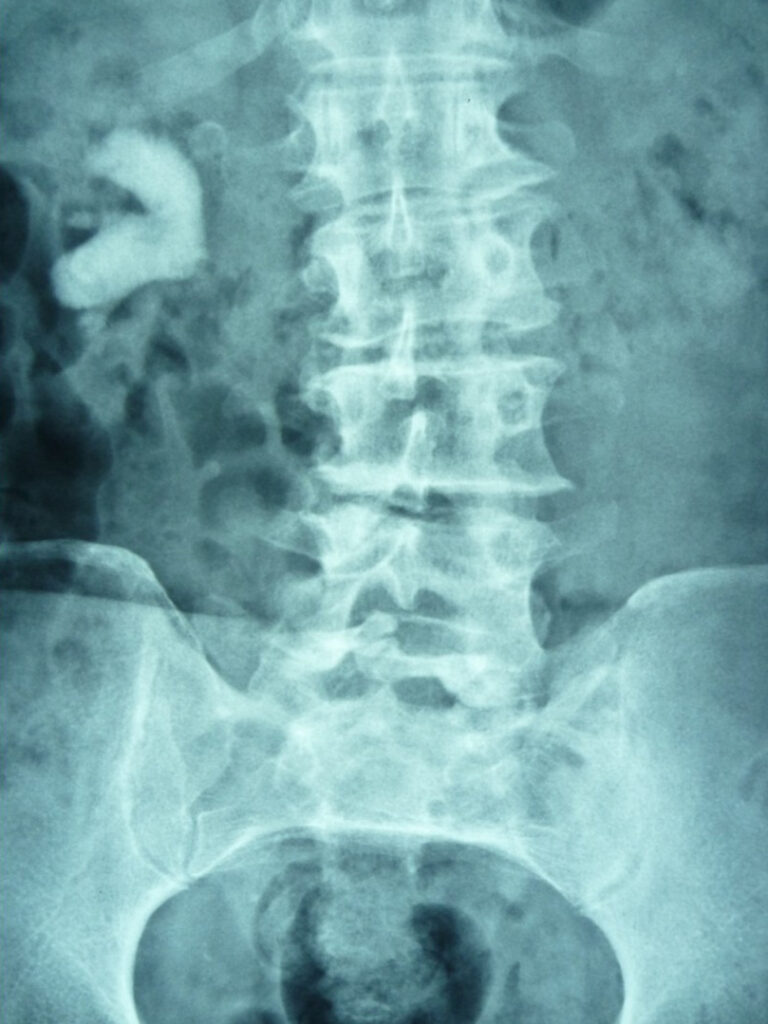

Kidney and ureteric stones (urolithiasis) are common — many patients will encounter renal colic or kidney stones at some point in their life. Stones range from tiny, symptomless crystals to large, complex “staghorn” calculi that occupy much of the kidney’s collecting system. Some stones pass without intervention; others must be treated promptly to prevent obstruction, infection, or permanent loss of kidney function.

Why location matters: a stone in the kidney may cause few symptoms, whereas the same stone lodged in the ureter often causes renal colic — severe, intermittent pain caused by ureteral spasm as the stone tries to move. If a stone obstructs urine flow, pressure builds in the kidney (hydronephrosis) and the kidney’s ability to recover becomes time-sensitive.

Before deciding on treatment, it is essential to know the stone’s size, shape, orientation, radiodensity and exact location — this imaging information guides whether observation, medical management, ureteroscopy, PCNL or laparoscopic removal is appropriate.